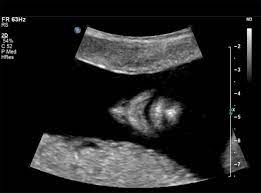

Trisomy 13 is often picked up at 12 weeks with an increased nt. Nosis of trisomy 18 to be made at the time of ultrasound examination. This is referred to as complete trisomy 13 or full trisomy 13. Overlap and difference in ultrasound findings trisomy 13 and trisomy 18. The amniocentesis came back positive for trisomy 13 (preliminary workup showed the abnormality in 97.5% of her cells). This is because each a. The most common abnormalities visualized are cardiac abnormalities, holoprosencephaly, omphalocele, and cleft lip/palate. Diagnosis of trisomy 13 on cvs should be followed up with amniocentesis and serial detailed ultrasound.

Now, this doesn't mean that the abnormalities aren't there. Trisomy 13 is typically due to having three full copies of chromosome 13 in each cell in the body, instead of the usual two copies. Patau syndrome (also known as trisomy 13) is considered the 3 rd commonest autosomal trisomy. Trisomy 13 and 18 are very different in terms of what you can see on ultrasound. Trisomy 13 represents the presence of an extra chromosome 13 resulting from a free copy or translocation. When an afp test indicates a high risk for trisomy 13, usually a level 2 ultrasound (also called a targeted ultrasound) is scheduled. The screening also determines risk of patau (trisomy 13) and edwards (trisomy 18) syndromes, rare and often fatal chromosomal abnormalities. If a maternal fetal dna test result comes back as high risk for a chromosomal abnormality, the recommendation (1) is to confirm the. Greater than 90% of fetuses with trisomy 13 have findings detected on prenatal ultrasound. Targeted sonography identified abnormal fetal anatomy or abnormal biometric measurements in 95% of fetuses with trisomy 13 in the second trimester after 17 weeks' gestation. Smith et al (1999) summarized the findings of 11 cases of trisomy 13 detected on cvs, of which, three cases had confirmed trisomy 13 mosaicism in the fetus. The purpose of this chapter is to focus on the evaluation and management of isolated ultrasound soft markers diagnosed in the second trimester. Fetal ultrasound during pregnancy can also give information about the possibility of trisomy 18 or 13, but ultrasound is not 100 percent accurate because some babies with trisomy 18 and 13 may look the same on ultrasound as those without the syndrome.

Identify major defects on the sonogram associated with trisomy 13. Fetal ultrasound during pregnancy can also show the possibility of trisomy 13 or 18. When ultrasound findings are consistent with trisomy 13, prenatal karyotyping should be undertaken. Greater than 90% of fetuses with trisomy 13 have findings detected on prenatal ultrasound. This is referred to as complete trisomy 13 or full trisomy 13. After completing this course, the participant should be able: Fetal ultrasound during pregnancy can also give information about the possibility of trisomy 18 or 13. But ultrasound is not 100% accurate. Fetal ultrasound during pregnancy can also give information about the possibility of trisomy 18 or 13, but ultrasound is not 100 percent accurate because some babies with trisomy 18 and 13 may look the same on ultrasound as those without the syndrome. The nt ultrasound is done between 11 and 13 weeks, when baby's nuchal translucency, the clear tissue located at the back of a developing baby's neck, can be measured. Targeted sonography identified abnormal fetal anatomy or abnormal biometric measurements in 95% of fetuses with trisomy 13 in the second trimester after 17 weeks' gestation. Smith et al (1999) summarized the findings of 11 cases of trisomy 13 detected on cvs, of which, three cases had confirmed trisomy 13 mosaicism in the fetus. Targeted sonography identified abnormal fetal anatomy or abnormal biometric measurements in 95% of fetuses with trisomy 13 in the second trimester after 17 weeks' gestation.